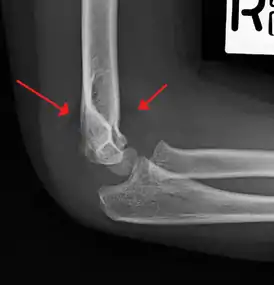

Supracondylar humerus fracture

| An elbow X-ray showing a displaced supracondylar fracture in a young child | |

A supracondylar humerus fracture is a fracture of the distal humerus just above the elbow joint. The fracture is usually transverse or oblique and above the medial and lateral condyles and epicondyles. This fracture pattern is relatively rare in adults, but is the most common type of elbow fracture in children.[1] In children, many of these fractures are non-displaced and can be treated with casting. Some are angulated or displaced and are best treated with surgery. In children, most of these fractures can be treated effectively with expectation for full recovery.[2] Some of these injuries can be complicated by poor healing or by associated blood vessel or nerve injuries with serious complications.